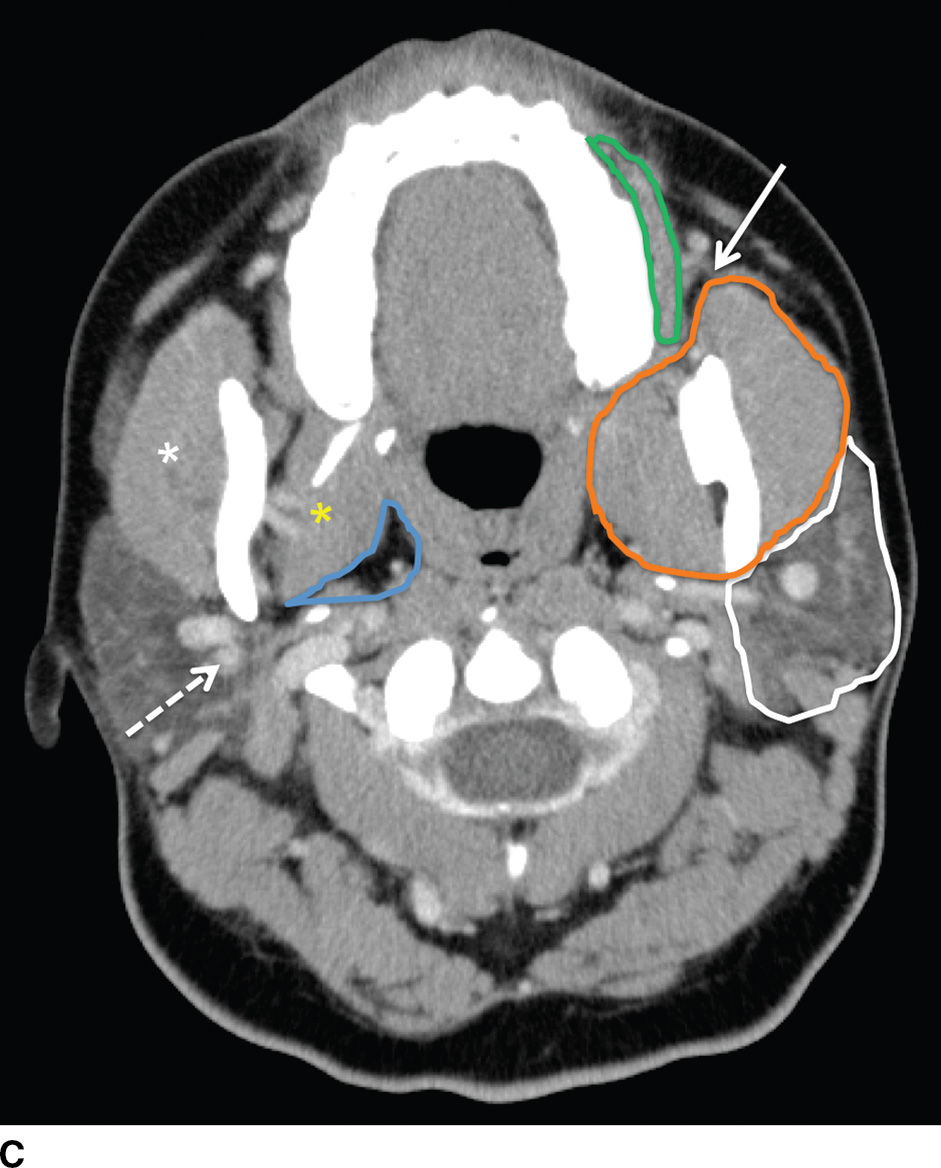

A representative example of an accessory parotid gland. A softtissue Accessory Organ Parotid Gland Three pairs of major salivary glands (parotid, submandibular, and sublingual glands) and numerous smaller ones secrete saliva into the. Protrusion of the parotid gland anteriorly over the anterior edge of the ramus of the mandible and continuity with the main gland. The parotid gland extends from the posterior border of the ramus of the mandible to the upper portion of. Accessory Organ Parotid Gland.